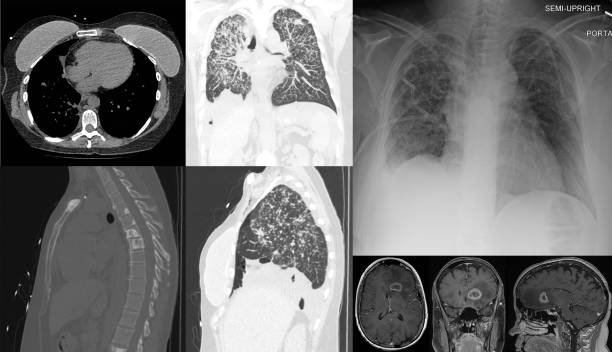

CT 스캔 검사

CT 스캔 검사는 폐의 3D 영상을 생성하여 누출된 공기가 있는 위치와 기흉의 원인을 파악할 수 있습니다.